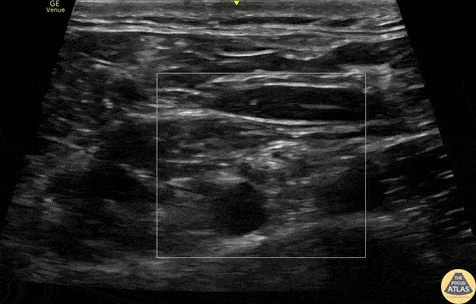

40s M presented with shoulder pain after a fall at work, and radiographs confirmed a proximal humerus fracture. As the patient was neurovascularly intact and had a closed fracture, conservative management in a sling was planned by orthopedic surgery. To augment pain control, a supraclavicular brachial plexus block was performed using bupivacaine and dexamethasone. The block is shown here, with color doppler first used to identify the carotid artery and confirm the absence of vascular flow in the region of the brachial plexus. The supraclavicular brachial plexus is seen at the center right of the image, just lateral and adjacent to the pulsating carotid artery with color flow. The first rib is seen just deep to the artery and plexus, providing a physical backstop to avoid inadvertent pneumothorax. An in-plane technique was used to advance the needle and anesthetic was deposited just superficial to the brachial plexus. The patient had improvement of his pain and was able to be discharged with outpatient orthopedic follow up. Dr. Lindsay Howe, PGY3 Denver Health Residency in Emergency Medicine